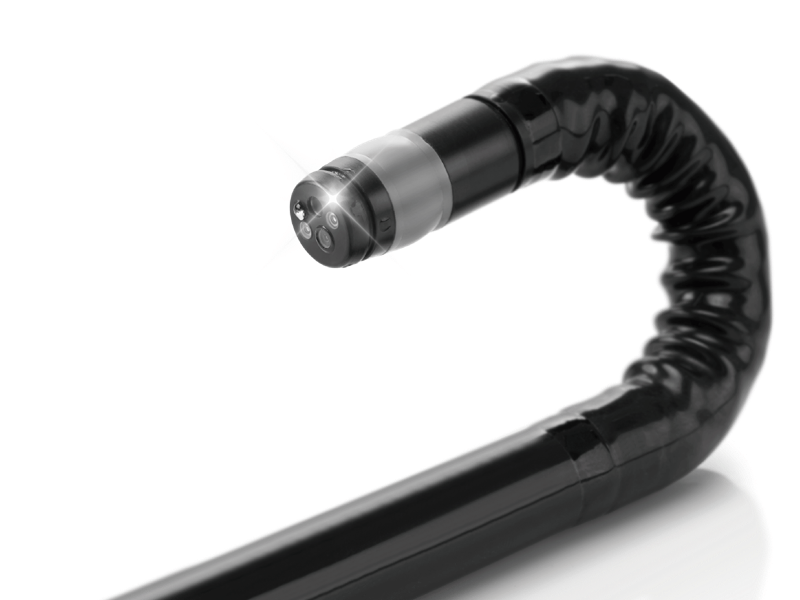

优越的弯曲角度,更小的弯曲半径,为医生提供了更好的操控手感

物镜清洗功能使内镜视野保持清晰

360°电子环形扫查与高清内镜影像相结合,提供了良好的插入性能和高清的内镜图像

卓越的宽频设计,满足医生探查不同深度的组织和器官

搭配独立超声主机,为临床提供更优质的超声画质